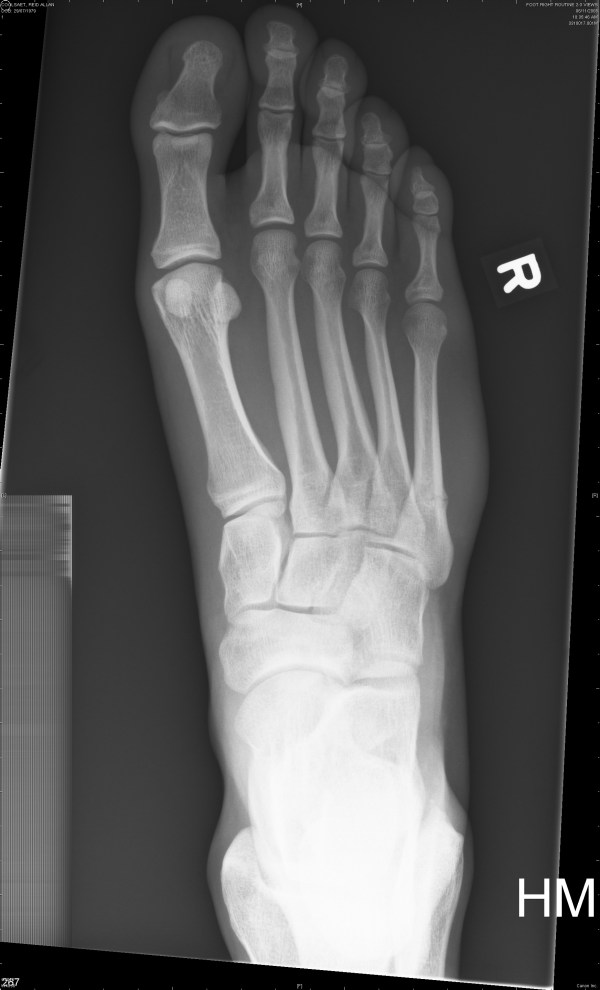

The first two are from November 6th and the last two are from November 22nd.

The fifth metatarsal (long bone on the far right) is broken.

Nov. 22